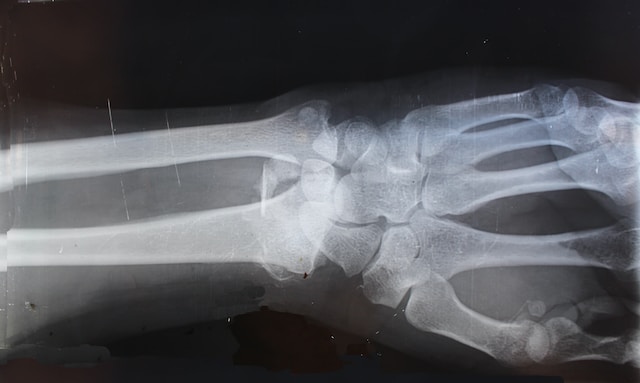

בית משפט השלום ברמלה פסק לאחרונה פיצויים של כ-283 אלף שקל לאישה בת 75 שלפני כ-7 שנים נדרסה על-ידי קלנועית בראשון לציון, ושברה את הירך. מאחר שהנהג הפוגע נפטר השופט דב גוטליב חייב את שלושת ילדיו ואלמנתו לשלם את הפיצויים בהתאם לחלקם בירושה. בכך, נדחתה טענתם כי מדובר בתאונת דרכים. נקבע כי בפסיקה הוחלט להוציא את הקלנועיות מתחולת החוק לפיצוי נפגעי תאונות דרכים כדי להקל קשישים ונכים מבחינת רישיון וביטוח.

התובעת עמדה על המדרכה ברחוב הרצל וחיכתה למונית כשלפתע נהג קלנועית שנסע על המדרכה פגע בה, הפיל אותה ארצה ועלה על הרגל שלה. את התביעה לפיצוי על נזקיה היא הגישה לאחר שנפטר ולכן היא הופנתה כלפי שלושת ילדיו מאשתו הראשונה ואלמנתו (אשתו השנייה) – כיורשיו.